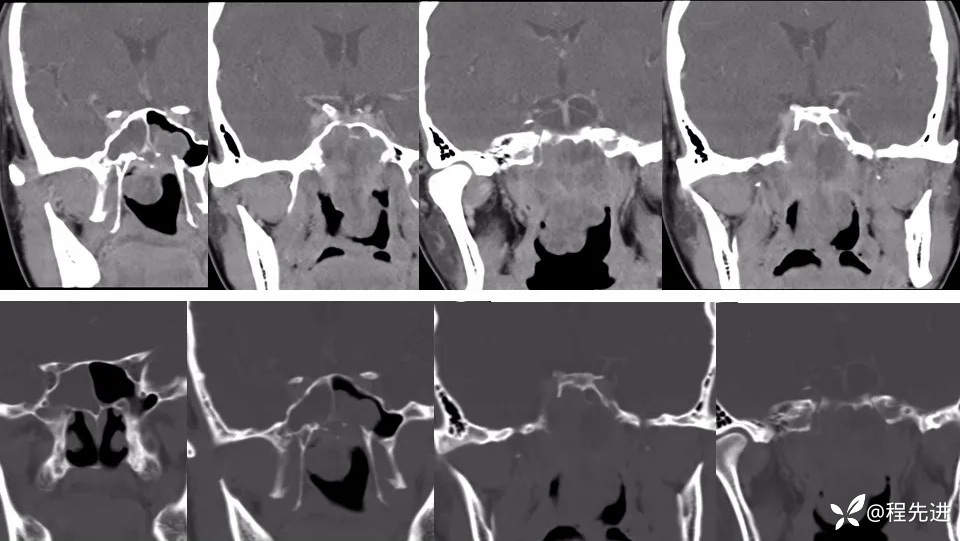

CT增强: